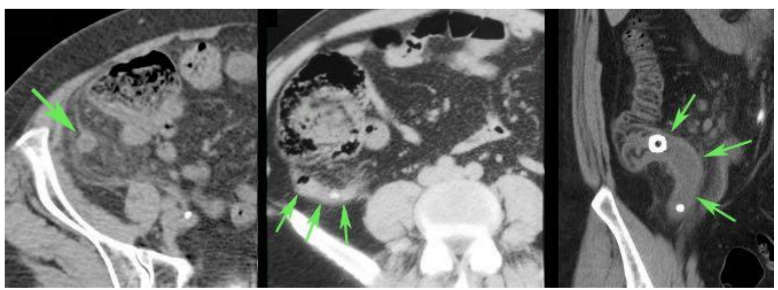

Bilddiagnostik – ultraljud/CT/MRI

• Appendix diameter > 6mm (ju större desto större risk), icke kompressibel (tyder på tryck), fri vätska, inflammerat fett.

När har ovan metoder ett värde?

A

Om kliniskt intermediär sannolikhet kan det vara lämpligt med CT

o Vid screening blir 20 % falskt positiva. Vid hög sannolikhet kommer 50 % vara falskt negativa.

o Om kliniskt låg sannolikhet – skicka hem patienten

o Om kliniskt hög sannolikhet – operera (titta in)